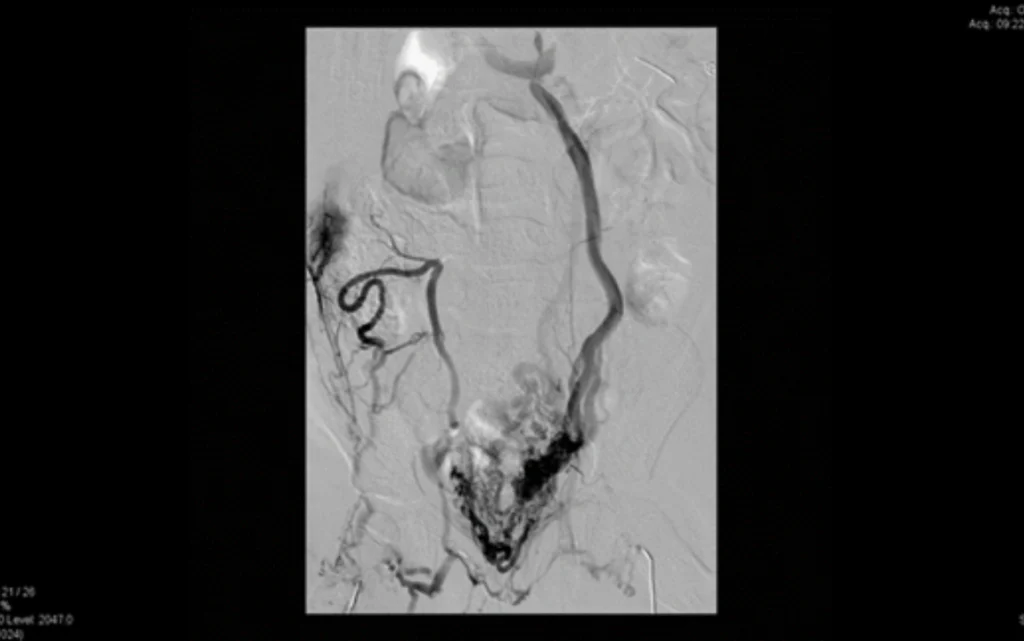

The pre-operative use of 3-D modelling of the vascular anatomy in children that have malformations of their vena cava and aorta.

Arterial anastomosis window

Picture of venous and aorta malformations and classification.

A4:V4 malformation